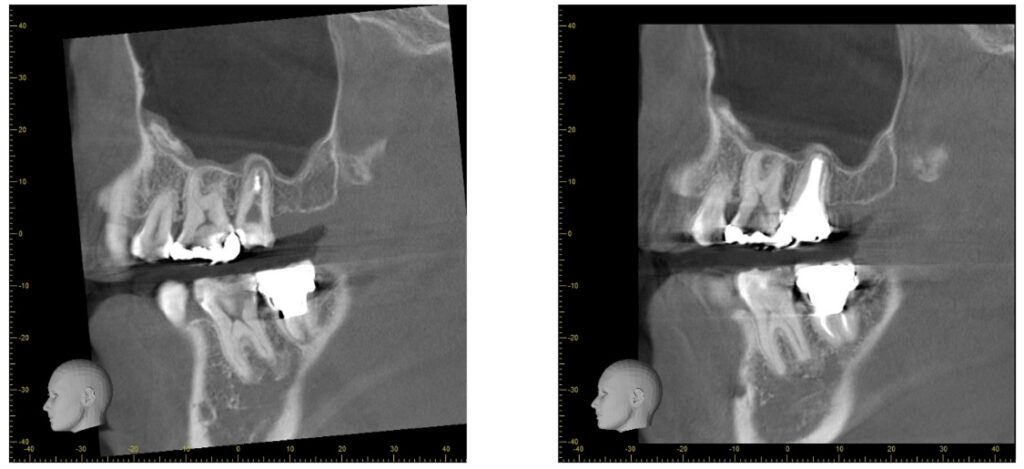

症例27:根尖性歯周炎

根尖部の炎症の改善、再感染の防止を行いました。